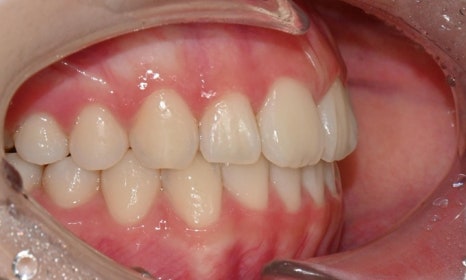

치료 후 전치부 배열이 정리되면서 웃을 때 스마일 라인도 한층 자연스럽게 개선되었습니다. 과개교합 역시 기능적으로 안정된 상태로 마무리할 수 있었습니다. 치료 후반부에 아주 경미한 중심선 차이가 남아 추가 장치를 통한 마무리를 권유드렸으나, 환자가 고2 학생으로 학업 일정이 바쁜 시기였고 현재 결과에 대해 본인과 보호자 모두 충분히 만족하여 이 상태에서 치료를 종료하기로 하였습니다.

치료 전후 스마일 라인 - 연세정원치과

무엇보다 이 환자는 8개월 동안의 치료 전반에 걸쳐 장치 착용을 매우 잘 지켜준 성실한 학생이었고, 그 결과 비교적 33단계의 효율적인 장치 갯수만으로도 안정적이고 만족스러운 결과를 얻을 수 있었습니다.

성장기 학생들의 교정 치료에서는 학업에 대한 부담, 외모 변화에 대한 걱정, 그리고 치료 기간이 중요한 고려 요소가 됩니다. 이번 케이스처럼 비교적 경미한 과개교합과 전치부 총생의 경우, 인비절라인은 일상생활과 학교생활에 큰 지장 없이 교정을 진행할 수 있는 좋은 방법이 될 수 있습니다. 또한 환자의 협조도가 좋은 경우, 비교적 효율적인 치료 계획으로도 안정적인 결과를 기대할 수 있습니다.